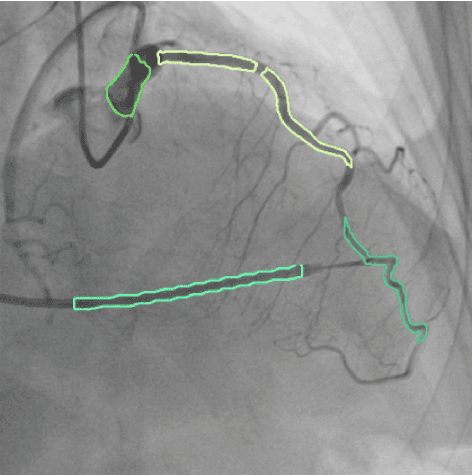

Abstract:Accurate segmentation of coronary arteries is a pivotal process in assessing cardiovascular diseases. However, the intricate structure of the cardiovascular system presents significant challenges for automatic segmentation, especially when utilizing methodologies like the SYNTAX Score, which relies extensively on detailed structural information for precise risk stratification. To address these difficulties and cater to this need, we present MPSeg, an innovative multi-phase strategy designed for coronary artery segmentation. Our approach specifically accommodates these structural complexities and adheres to the principles of the SYNTAX Score. Initially, our method segregates vessels into two categories based on their unique morphological characteristics: Left Coronary Artery (LCA) and Right Coronary Artery (RCA). Specialized ensemble models are then deployed for each category to execute the challenging segmentation task. Due to LCA's higher complexity over RCA, a refinement model is utilized to scrutinize and correct initial class predictions on segmented areas. Notably, our approach demonstrated exceptional effectiveness when evaluated in the Automatic Region-based Coronary Artery Disease diagnostics using x-ray angiography imagEs (ARCADE) Segmentation Detection Algorithm challenge at MICCAI 2023.